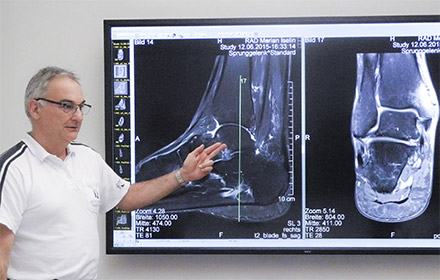

UHD 8MP Displays deliver extreme detail & patient confidence

Efficient communication and discussion between patients and cooperating physicians is crucial for success. “Modern medicine is team work”, says Dr. Egelhof. “It works best, if you can assess and discuss the examination results together with the doctors involved and the patients. For this purpose, the image display must be so precise that from the different viewing angles and distances in the meeting room good conditions are found, to carry out and obtain a profound analysis.”

Common diagnostic monitors were not suitable for this purpose, as they are far too small for larger groups of people to gather around. Previously used large-format display technologies offered only lower resolutions and therefore could not display detail with the precision nor colour nuances required. The hospital was seeking a new solution, one which would meet their requirements for resolution, colour quality and signal processing in UHD quality, whilst impressing on patients and physicians that they are a meticulous care provider.

The Merian Iselin Hospital selected the NEC MultiSync® X841UHD 8MP monitor featuring a screen diagonal of more than two metres and DICOM mode for clinical review of x-ray images for use in the MDT room. An NEC MultiSync MD322C8, with the same resolution as the large-format display, is used as an input monitor for the radiologists.

The extreme detail achieved with the UHD resolution display permits more precise diagnoses and allows extremely low viewing distances. Medical image data is reproduced correctly thanks to precise calibration and DICOM mode. “Black is really shown as black, just like white is really white on the screen”, says Dr. Egelhof with delight. A semi-matt surface restricts the effect of reflections on the screen.

The diagonal dimensions of more than two metres allow several images to be shown alongside each other for direct comparison. The sheer size permits groups of up to 10 people to gather in front of the screen with unrestricted views. Thanks to the high display brightness, images remain stable regardless of the ambient room lighting. Whilst in operation, the monitor does not emit any audible sound, therefore concentration is not impaired, even in larger groups or sensitive meeting situations.

“The Merian Iselin Hospital offers its customers and patients best service and highest quality. Therefore, the requirements which the hospital imposes on itself, also apply to the technical equipment”, says Christoph Kreutner, Technical and IT Manager of the hospital. “The discussion of the x-rays is now possible for the first time at the highest level, as the image can now be shown in the same quality and grade as on the diagnostic monitor.”

“A good diagnostic monitor says more than 1000 diagnostic words”, says Dr. Egelhof. “With the use of the new meeting room resolution, the diagnostic work could be visualised and thus the credibility of the findings could be increased, as the lesions are shown in a better and more precise manner.” This leads to less uncertainty for all involved and increases productivity both in radiology itself as well as referring physicians and other incorporated medical specialisations.